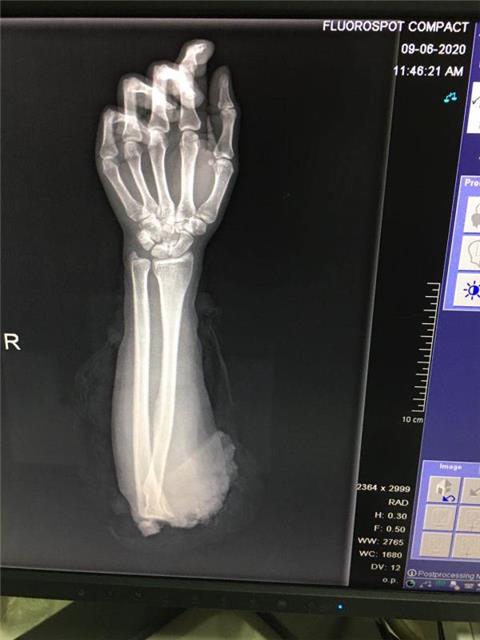

送锦旗的是一位29岁的患者,她告诉记者,在上个月初因为右肘关节被机器绞伤完全离断在3OO医院得到了非常及时的救助。目前再植肢体成活,一期功能康复训练结束,可以回家疗养等待下一步治疗。